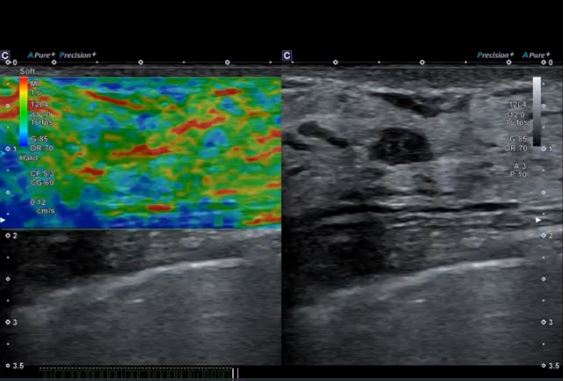

Нова вдосконалена технологія компресійної елестографії Strain Elastography забезпечує покращену часову та просторову роздільну здатність, високу відтворюваність і дозволяє вибирати ROI навіть після замороження кадру.